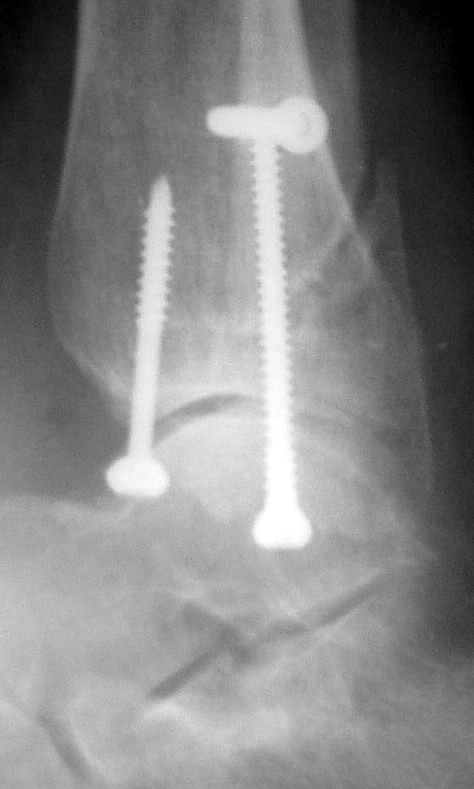

12 января прямой

|

12 января боковой

12 января трехчетвертной

Вариант с артродезом уже обсудили. Хотя, после увиденых снимков, пессимизм насчет восстановительной операции у меня, например, несколько уменьшился. Особенного уж какого-то остеопороза не видно даже на январских снимках. Можно черед мини-доступы убрать винты, аппаратом вправить малоберцовую кость, устранить подвывих стопы. Ну а дальше фиксировать малоберцовую пластиной сзади. А может, и напряженной Y-спицей попробовать - Анатолий Федорович, как Вы полагаете? Внутреннюю - то, что осталось, если уже не получится сделать спицами и проволокой, то что-то типа пластики дельтовидной связки. А может, и не трогать ее вовсе... В общем, выбор непростой,

много факторов надо взвесить.

Если до сих ничего не сделано, с артродезом сустава в данный момент я бы повременил, на выставленных январских снимках хорошо сохранившийся сустав, а в "мортиз" (трехчетвертной) и на боковых снимках не менее 5 мм укорочение малоберцовой кости. Косые переломы лучше фиксировать пластинами, как то мы разбирали случай, где было отмечено, что это закон "таранная кость всегда следует за малоберцовой".

тарнная кость находится в латеральном подвывихе, что снижает шансы этого сустава.

Это видно по снимку - середина суставной поверхности тарана должна быть против середины суставной поверхности тибии. Причины, что это не так:

1. Внутренняя лодыжка не на месте

2. наружная лодыжка укорочена

3. Возможно есть компрессионный перелом наружной части пилона тибии.

В подобных случаях лучше всего начинать с главной цели - вправить таран, временно зафиксировать спицами и используя таран как шаблон поставить на место лодыжки, неважно в какой последовательности.